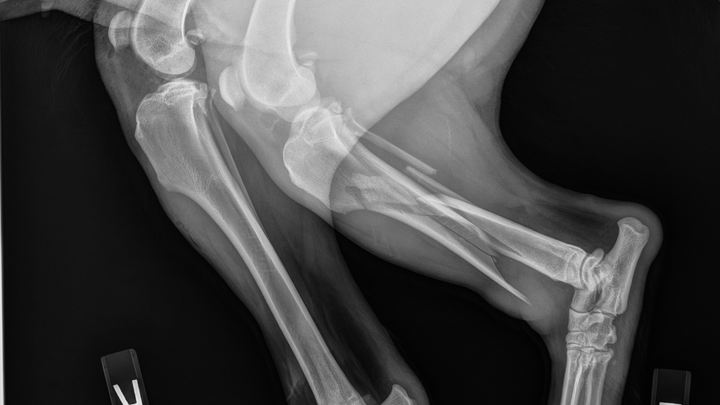

We heard the impact and found her badly injured. She was rushed to the emergency vet, where X-rays showed multiple fractures in her back leg.